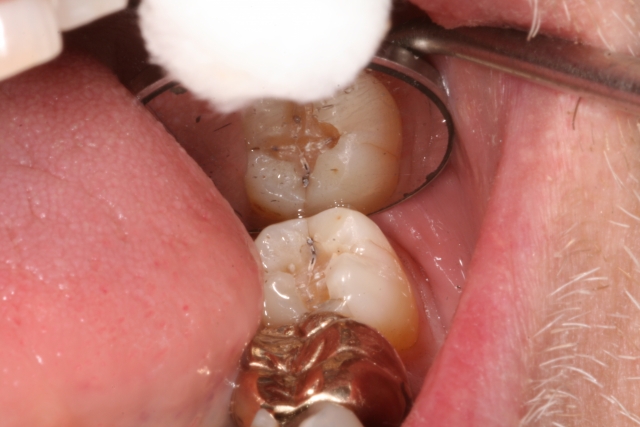

Many times, cracks/fractures are found in teeth on a daily basis in the restorative practice, especially after removing an existing restoration, having little to no symptoms. This can be described as an incomplete fracture if it involves one marginal ridge and a complete fracture if it involves both marginal ridges. It is a silent situation until the fracture worsens.

Hence, the reason I have described this as a silent epidemic: it is often an observation in our patients well before it becomes symptomatic with pain and sensitivity, leading to a diagnosis of a cracked tooth syndrome. In a recent study,1 cracks in teeth were histologically detected and cracks in all teeth were colonized by bacterial biofilms. When the cracks reached the dentin, dentinal tubules were invaded by bacteria, leading to inflammatory cell infiltration into the adjacent pulp tissue. The pulpal response is “based on the location, direction, and extent of the crack.”1 Not only do we have to be concerned about overall structural stability of the tooth and fracture, we also have to keep in mind that bacteria are invading the fracture/crack as well and have to be managed.

If your patient comes in with no symptoms, how and when can you tell if a tooth is cracked without symptoms? First and foremost, magnification and visualization are key components. How much magnification? Often in general dental practices, we utilize loupes up to six times magnification along with intraoral cameras to help see and diagnose cracks, but 13 times is the minimum needed to seek cracks/fractures visually.2,3 It has been shown that we can also use staining such as with methylene blue in addition to magnification to help identify cracks.4

We can also use a high-intensity, focused light for transillumination to help us visualize incomplete fractures/cracks in teeth. Without proper magnification and other techniques (use of a surgical operating microscope, which is found on a regular basis in most endodontic practices), and with no symptoms present, fractures in teeth can be challenging to visualize and/or identify and subsequently, to treat appropriately.

Visually, we have to be observant of our patients and look for wear facets, cracked restorations, hypertrophy in jaw muscles, and other missing teeth, craze lines, etc. We also must do an examination that ideally reproduces the symptoms that the patient is experiencing, but also know that just because we can’t reproduce the symptoms, it does not mean the tooth is not cracked. We need to do an examination looking closely at the area in question, as well as exploring the tooth in a tactile way for any “sticks,” pain or irregularities of the tooth surface. This can be done by variety of methods, including bite tests (a Tooth Slooth is a nice tool to use and isolate individual cusps/teeth), vitality testing, magnification, transillumination, visual and tactile examination, periodontal probing for isolated pockets, radiographic examination, including CBCT 3D exams, and even removal of an existing restoration.